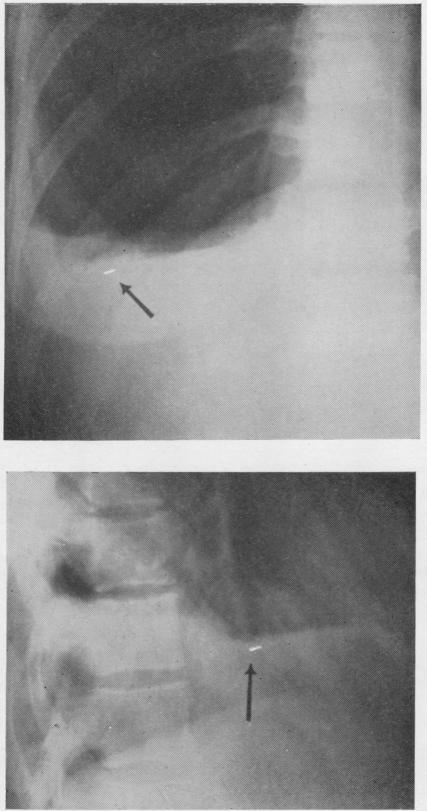

Thorax. 1954 Sep;9(3):226-8. doi: 10.1136/thx.9.3.226.